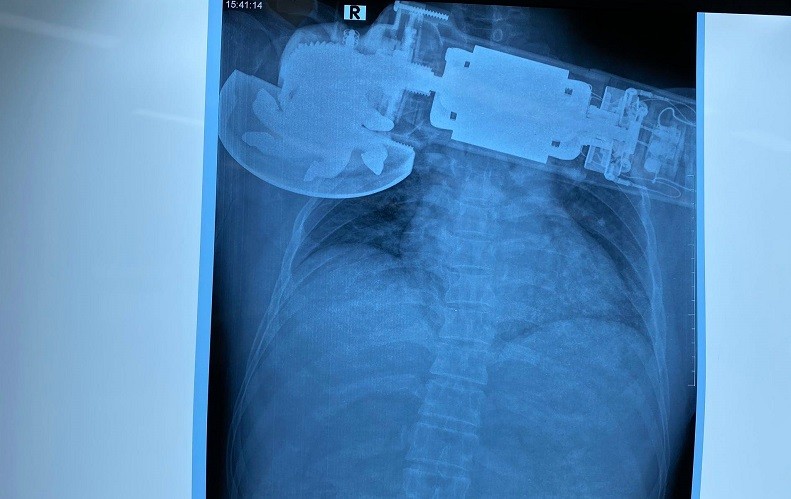

Máy chà cắm găm vào ngực phải của bệnh nhân.

Chiều 12-10, Bệnh viện Trung ương Quân đội 108 đã tiếp nhận một trường hợp ở Bắc Ninh bị máy chà văng, cắm găm vào ngực phải. Bệnh nhân được chỉ định mổ cấp cứu xử trí vết thương.

Theo lời kể của bệnh nhân, khi đang làm việc, bệnh nhân bất ngờ bị máy chà văng vào áo rồi cuốn vào ngực phải. Bệnh nhân được đưa vào Bệnh viện TƯQĐ 108 trong tình trạng tỉnh, vết thương không chảy máu, không khó thở, huyết động ổn.

Sau khi khám, các bác sĩ thấy máy chà găm sâu vào thành ngực phải, sát bờ dưới xương, bờ mép vết thương nham nhở, phần mềm thành ngực bị cuốn vào trong máy chà gây khuyết hổng phần mềm, mất da và bầm dập da quanh tổn thương.